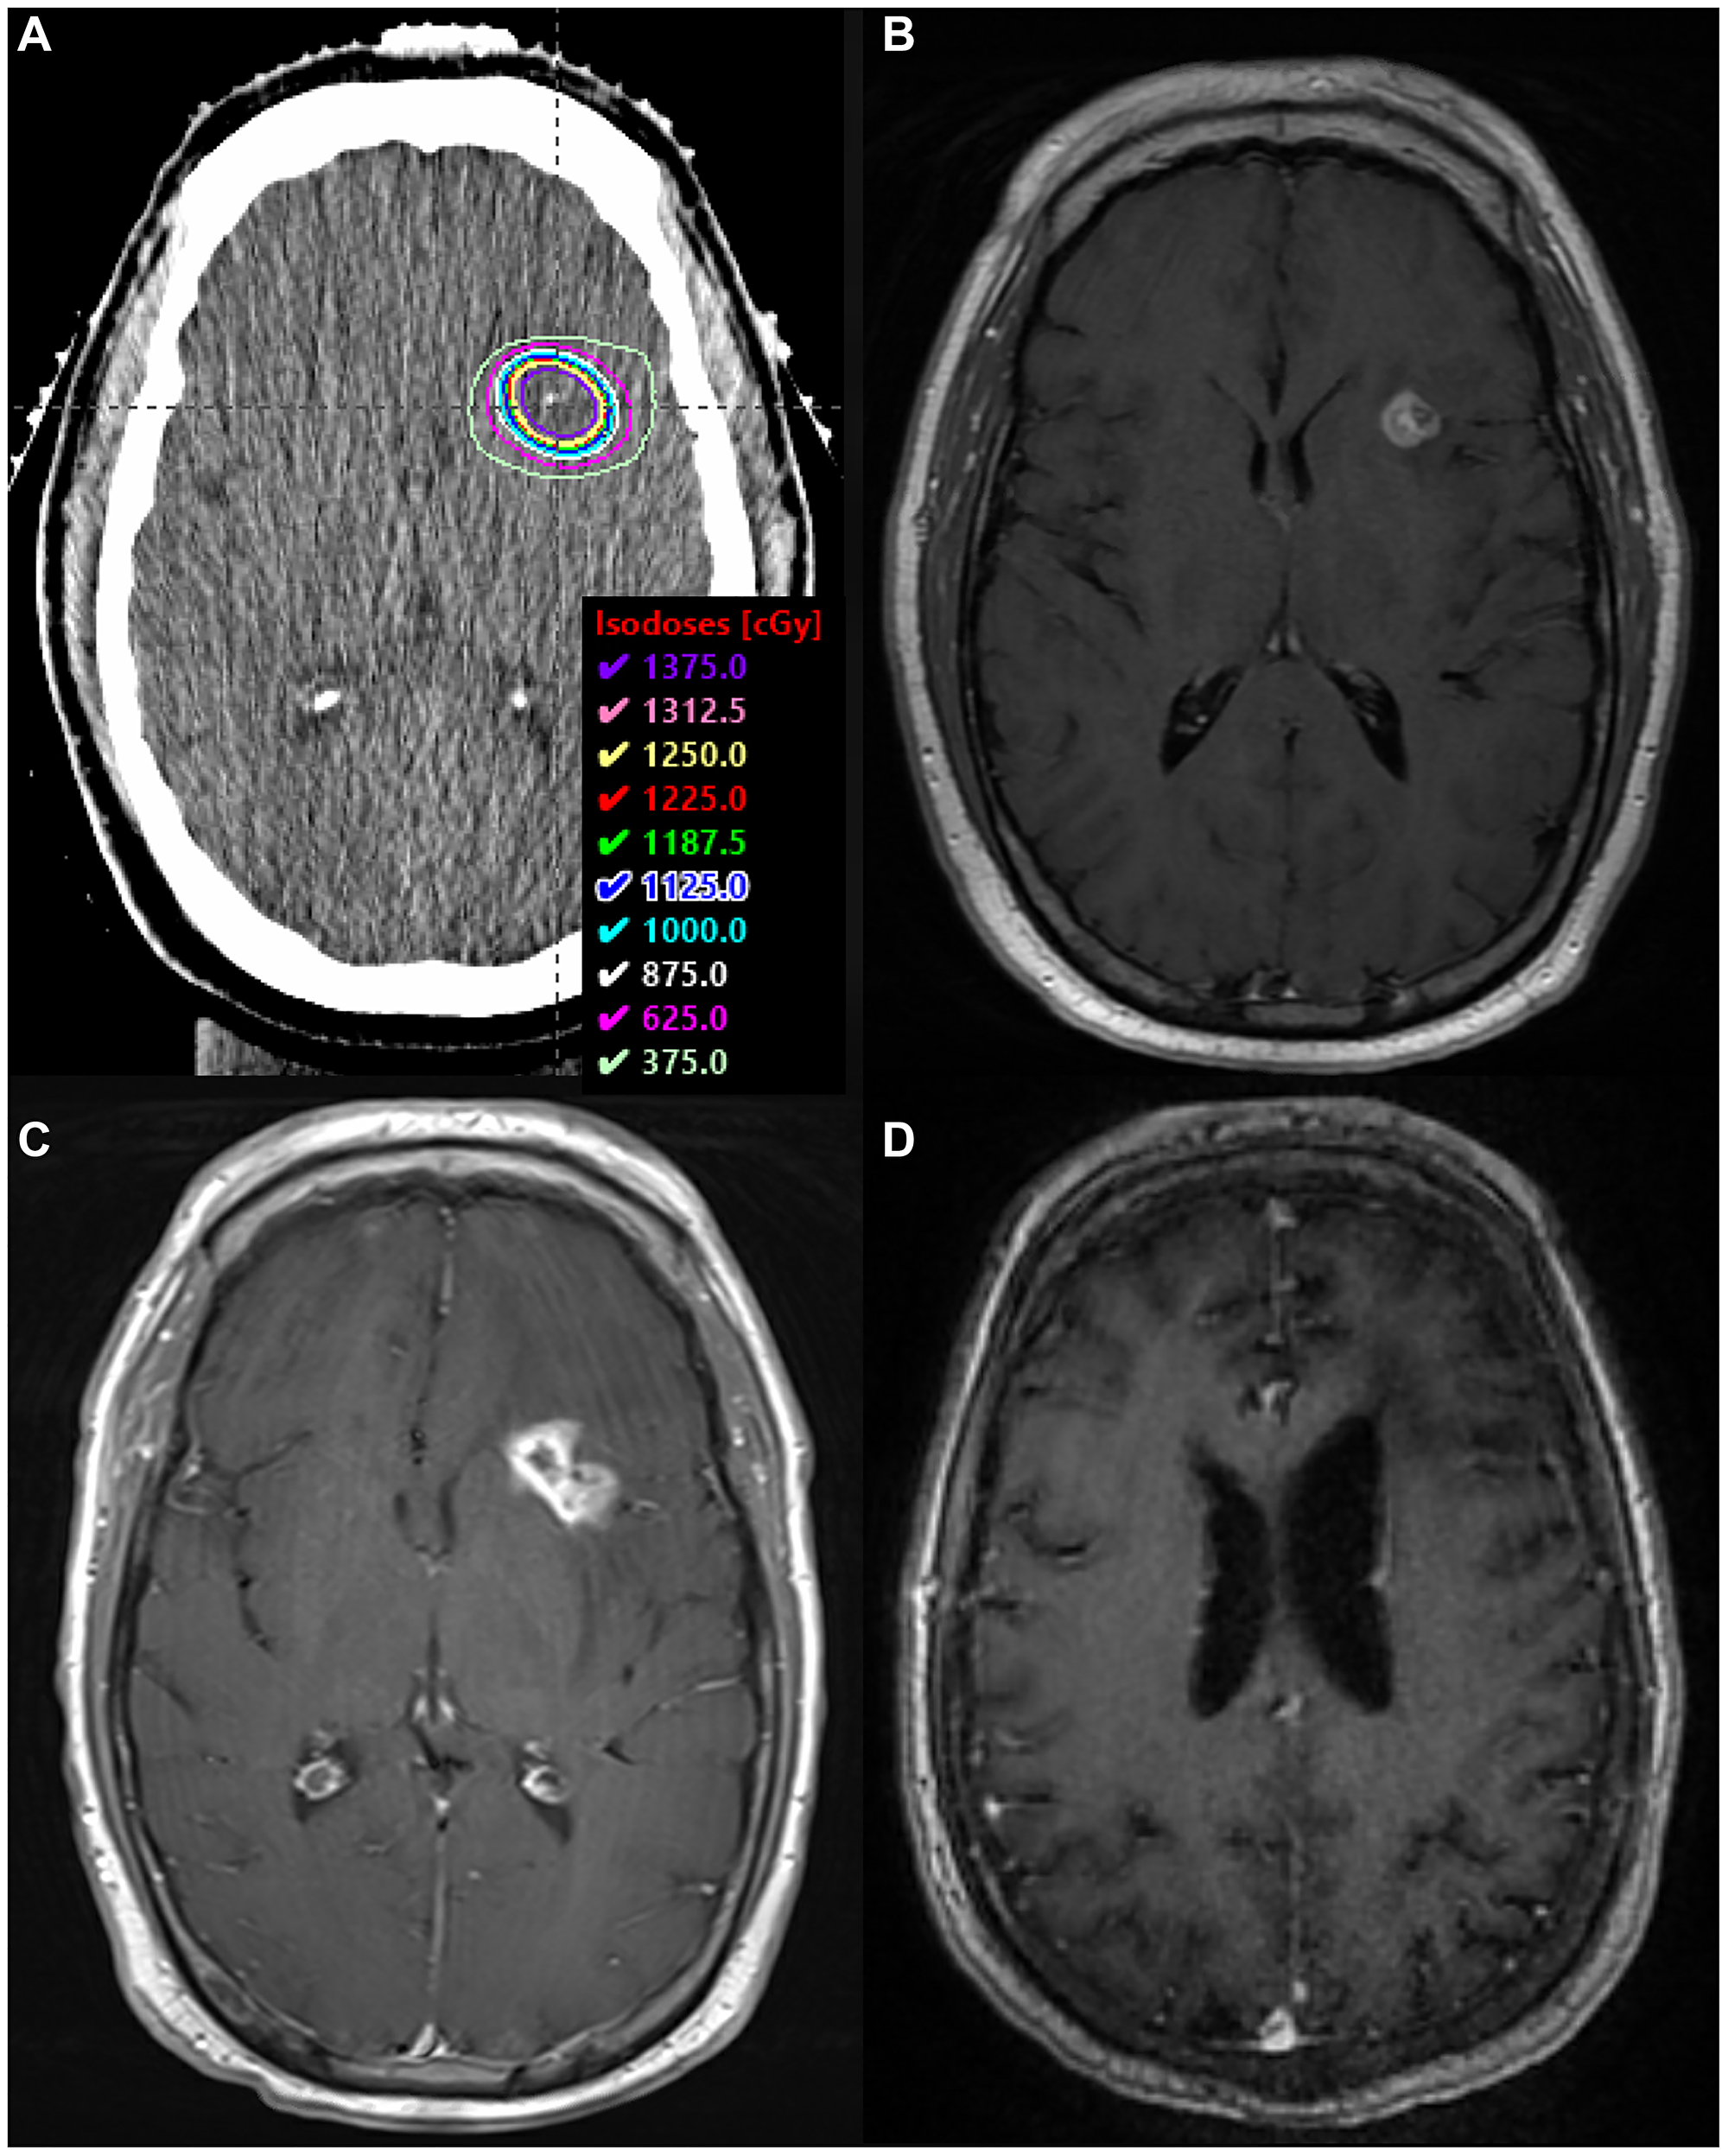

The patient was initiated on methotrexate (3.5 gm/m2) every 2 weeks for 6 cycles with concurrent weekly rituximab (RTX) (375 mg/m2) for 4 cycles, then every 2 weeks for 2 additional cycles. She received leucovorin rescue (20 mg) IV beginning 24 hours after each methotrexate infusion and was kept on dexamethasone 2 mg daily. She remained on levetiracetam 500 mg orally twice daily for seizure prophylaxis and pentamidine monthly for PCP prophylaxis. Levetiracetam was increased to 1000 mg twice a day following a breakthrough seizure prior to cycle 4 of RTX. Repeat imaging after her 5th cycle of methotrexate revealed a 3.7 × 2.7 × 4.3 cm lesion with increased surrounding T2 signal abnormality within the right frontoparietal lobes and new extension into the corpus callosum, concerning for disease progression. Per our institution’s practice, she was treated with rd-WBRT followed by an SRS boost of 12.5 Gy to the residual enhancing volume present on MRI 1 week before the boost treatment (Figure 1A and 1B). She had a complete radiographic response and no recurrent seizures.

SRS boost treatment plan and MRI scans

Figure 1: SRS boost treatment plan and MRI scans. (A) SRS boost treatment plan. (B) Enhancing residual disease prior to SRS boost on T1 sequence with contrast. (C) Biopsy-proven RN along the margin of the anterior body of the right lateral ventricle, within the SRS boost volume, on T1 sequence with contrast. (D) MRI >4 years after BV, demonstrating complete radiographic response on T1 sequence with contrast.

The nodular enhancement/FLAIR signal in the right periventricular white matter remained stable for thirteen months, until surveillance imaging revealed a slight interval increase in enhancement (Figure 1C). Symptoms included new left lower extremity weakness and dizziness. PET/CT confirmed hypometabolic activity within the concerning lesion, and repeat biopsy revealed RN (Figure 2B). She received BV 7.5 mg/kg every three weeks for four total doses. She ultimately achieved a complete radiographic response, and symptoms resolved without necessitating steroids. She has had no evidence of progression for over four years (Figure 1D).